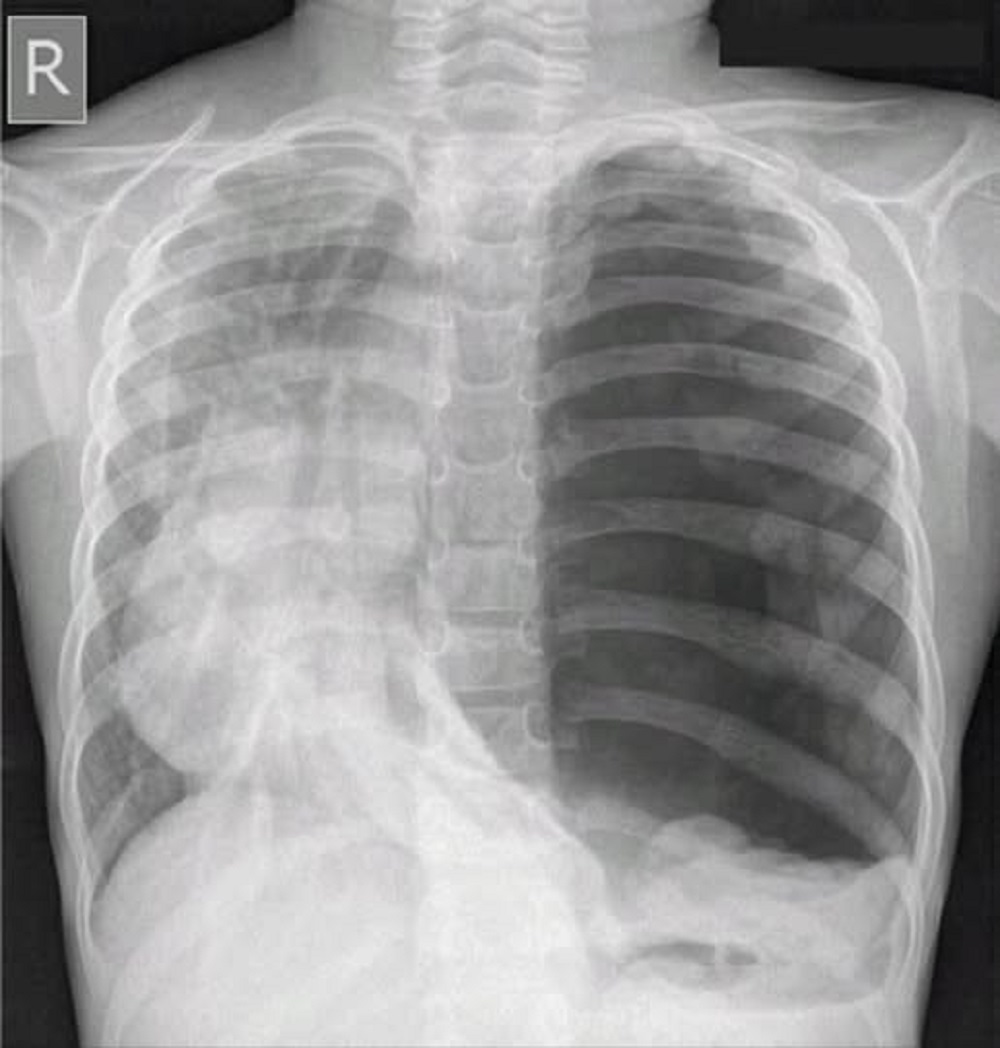

Los efectos ya se están presentando. Desde septiembre nos dimos cuenta que al toser echo humo por la boca. Soy una chimenea que camina y no es por el cigarro. El humo, como todo lo demás, huele a carbón. Ya preocupado, y en el decimosexto intento, logré hacerme una placa.

El especialista, al revisarla, me diagnosticó una enfermedad rarísima. Según él, tuvo que buscar información y pedir ayuda a varios colegas. La enfermedad se llama Neumotórax Carbónico Crónico. Se estima que con los gases resultantes de la quema, he acumulado en los pulmones más gas que el producido por Energas Matanzas. Algún partido tendré que sacarle a ésto.